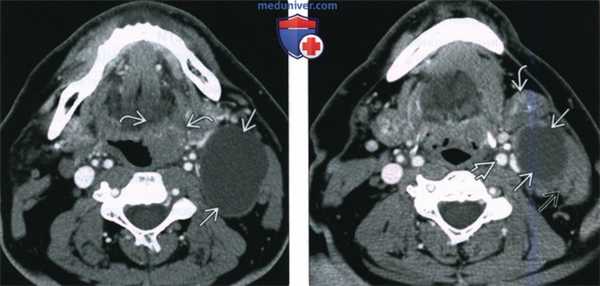

(Слева) При аксиальной КТ с КУ в левой половине шеи визуализируется большое однокамерное кистозное образование, имитирующее кисту второй жаберной щели по своему расположению. Обратите внимание на объемное образование в области нижнего полюса левой небной миндалины.

(Справа) При аксиальной КТ с КУ на более каудальном уровне визуализируется кистозно-некротическое объемное образование, расположенное снаружи от сонного влагалища, сзади от поднижнечелюстной слюнной железы спереди и изнутри от грудино-ключично-сосцевидной мышцы. Объемное образование напоминает кисту второй жаберной щели, но представляет собой метастаз ВПЧ(+) ПКР миндалины в лимфоузел.